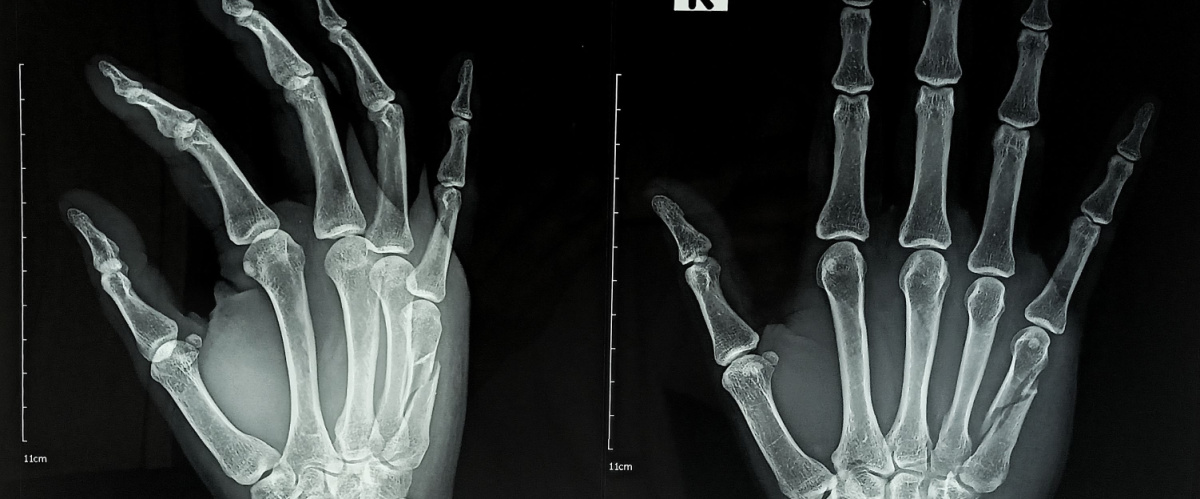

Tramite l’uso di raggi x che vengono indirizzati sulla parte da esaminare, in questo caso le mani, si possono ottenere immagini delle ossa. Queste infatti essendo più dense non lasciano passare i raggi come gli altri tessuti detti molli, pertanto quello che rimane è un’immagine bidimensionale della parte ossea.

↑ topServe per la diagnosi e il controllo dello stato di salute delle mani e delle ossa che le compongono.

In particolare serve per individuare:

- fratture delle ossa

- degenerazioni dovute a condizioni come l’artrosi delle mani

- infiammazioni come l’artrite

- eventuali formazioni iperplastiche che possono essere indice di neoplasie (metastasi ossee)